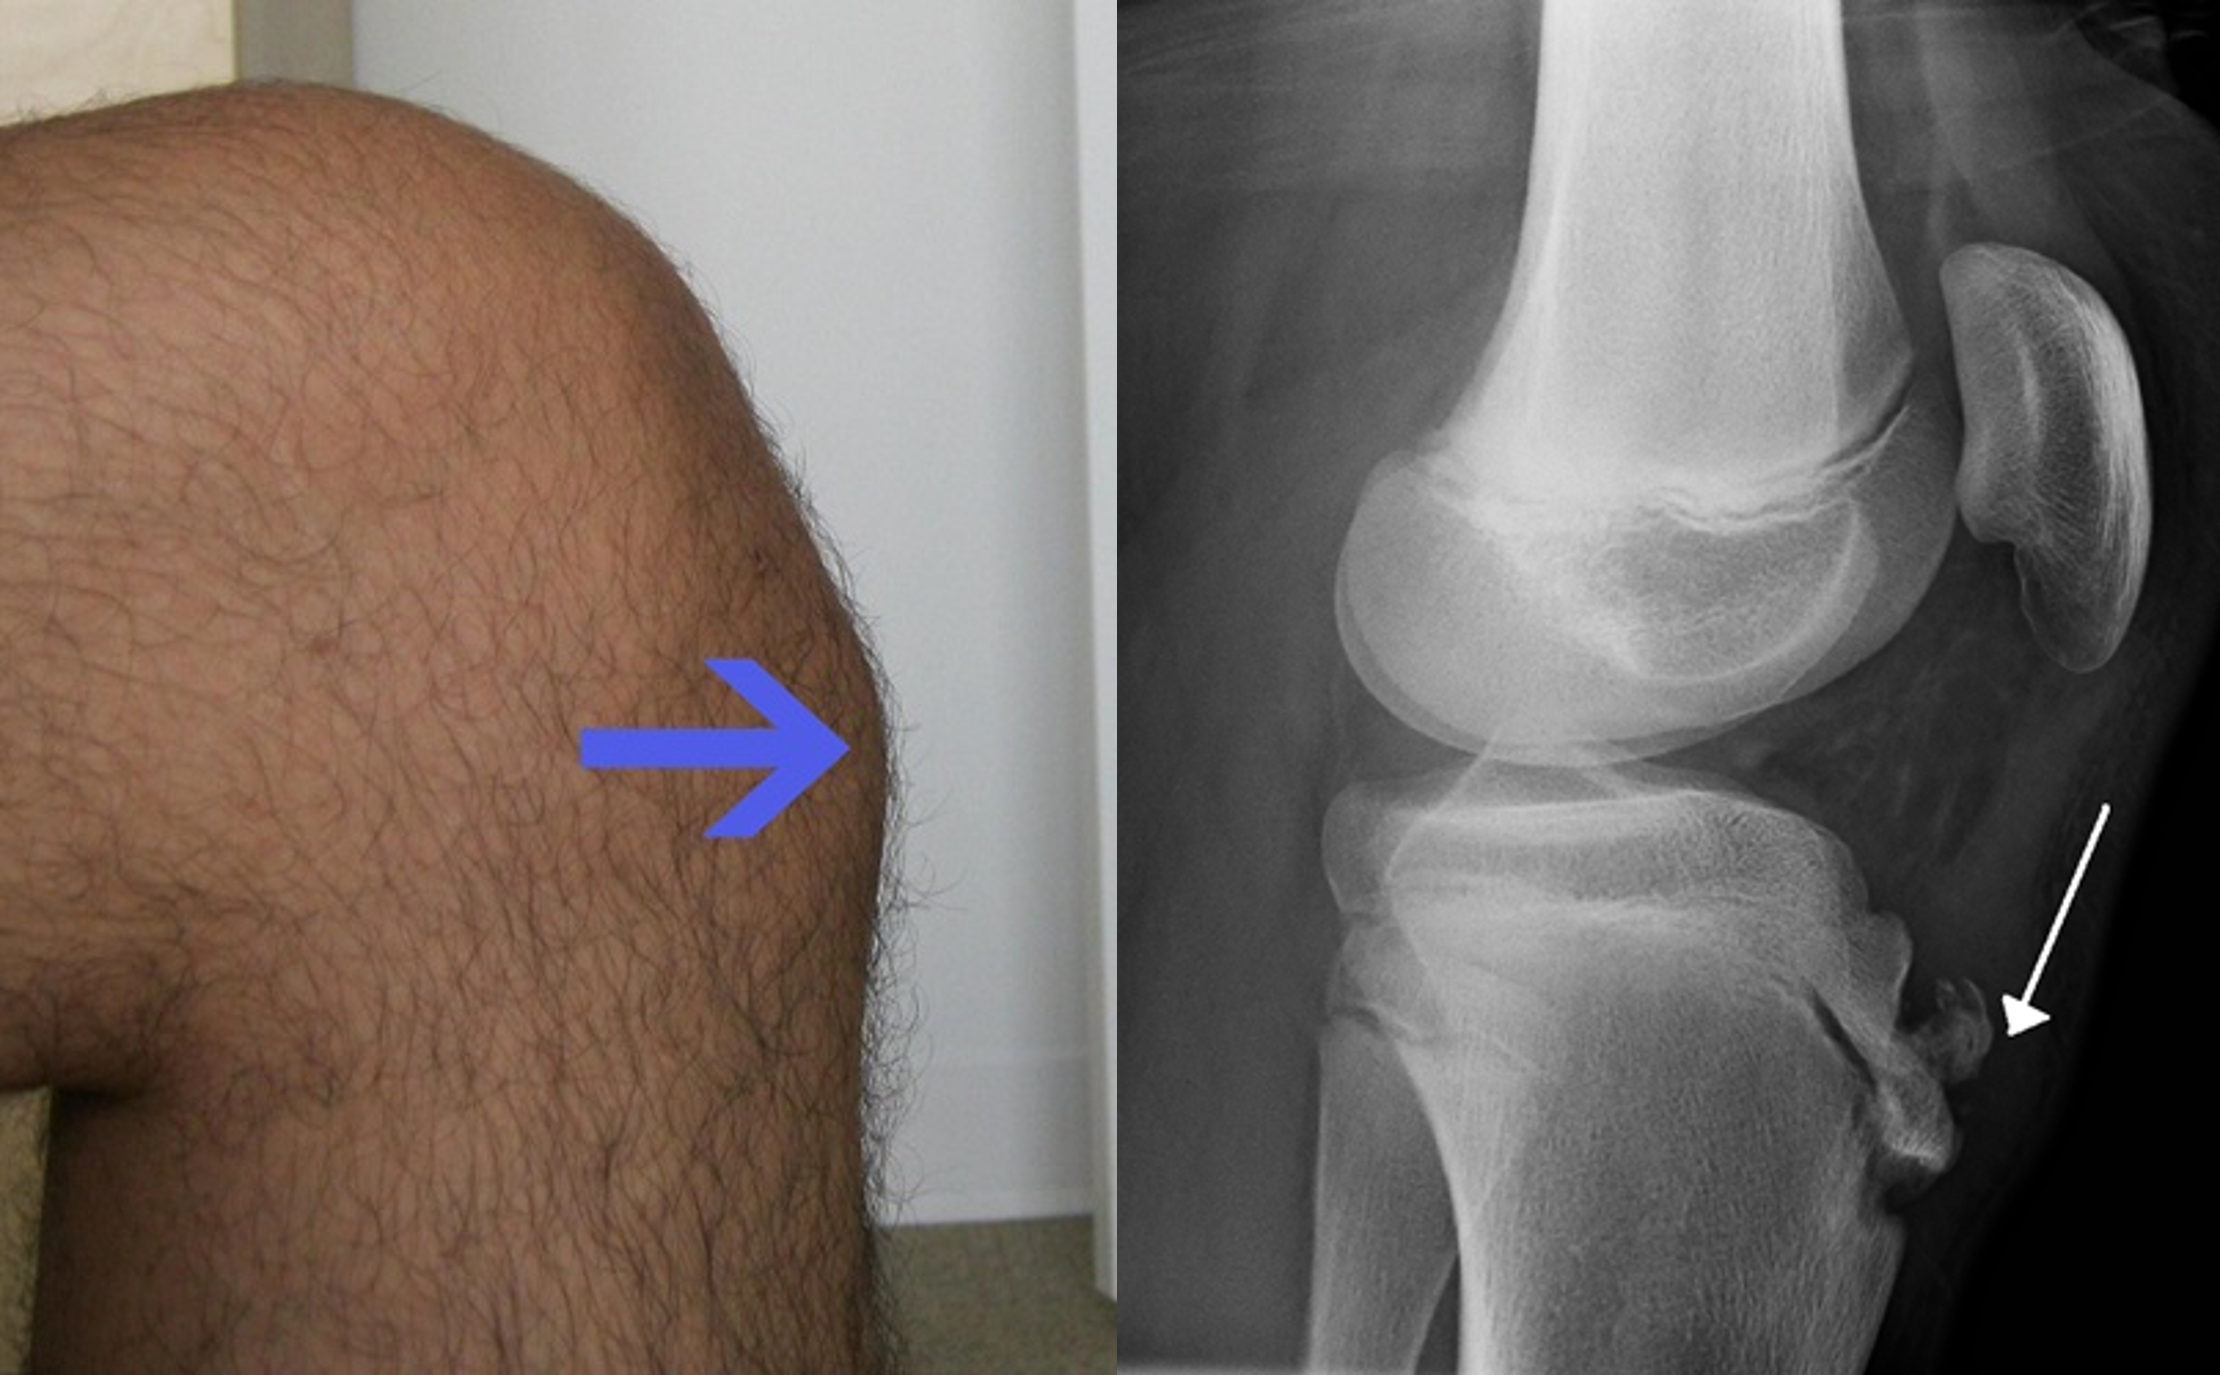

- En los adolescentes, es característico el dolor en la tuberosidad tibial (Osgood Schlatter).

- La enfermedad de Osgood-Schlatter es una inflamación del ligamento rotuliano en la tuberosidad tibial, generalmente afecta a los adolescentes durante los períodos de crecimiento acelerado.12 Se caracteriza por un bulto doloroso justo debajo de la rodilla que empeora con la actividad y mejora con el reposo.2 Los episodios de dolor suelen durar de algunas semanas a meses. Una o ambas rodillas pueden verse afectadas y los brotes pueden reaparecer.